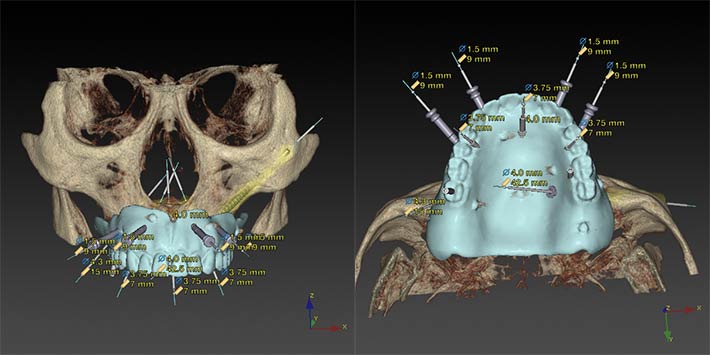

3Dシミュレーション

Nobel Clinician によるインプラント埋入の為の3Dシミュレーション

インプラント埋入手術と同時に術前に用意された固定式の補綴物を入れ、機能性と審美性を

短時間で回復する為に、即時荷重を前提としたインプラント治療計画です。

右上後方:Nobel Parallel CC 4.3 × 15㎜ で即時荷重が可能

前方領域:Nobel Parallel CC 4.3 ㎜(レギュラープラットフォーム)を入れる骨量がない為、ナロープラットフォーム3.75×7㎜を3本使用する事で即時荷重が可能

左上後方:通常のインプラントを入れる骨量がない為に、ザイゴマインプラントを使用する事で即時荷重が可能

術前のインプラント埋入ポジション